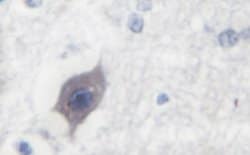

| Immunohistochemistry (Paraffin), Western Blot, Immunocytochemistry | |